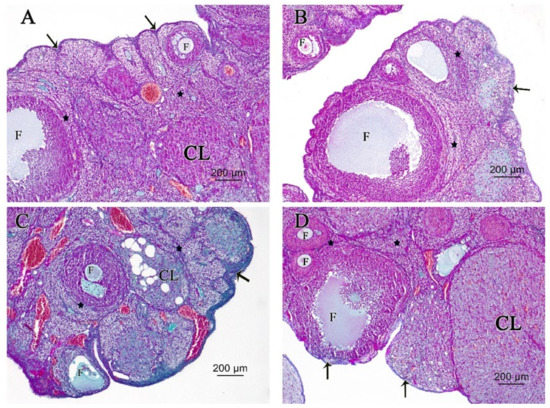

3.2.1. Ovarian Hematoxylin and Eosin (H&E)

3.2.2. Ovarian Periodic Acid-Schiff Reagent (PAS)

3.2.3. Ovarian Masson’s Trichrome (MT) Stain